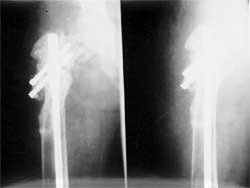

股骨远段骨折,4次钢板固定均失败,改用带锁髓内钉固定,7个月后骨折愈合。